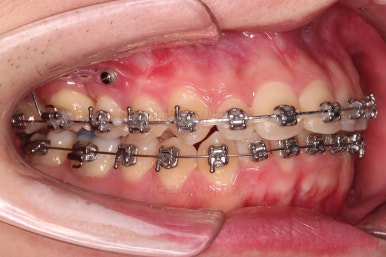

미니스크류가 식립되었고요.

결손치아도 오른쪽, 부정교합도 오른쪽이어서 오른쪽 위아래 각 1개씩 식립이 되었어요.

물론 윗니는 앞으로 당기는 용도, 아랫니는 뒤로 미는 용도였습니다.

중앙선과 교합을 고려해서 좀 더 밀고 당기기를 해주고 마무리를 하게 됩니다.

우측의 결손치아보다 뒤쪽에 있는 치아는 크기나 모양이 원래의 큰 어금니보다 작고 다르게 생겨서 100% 이상적인 교합을 얻기는 한계가 있었어요.